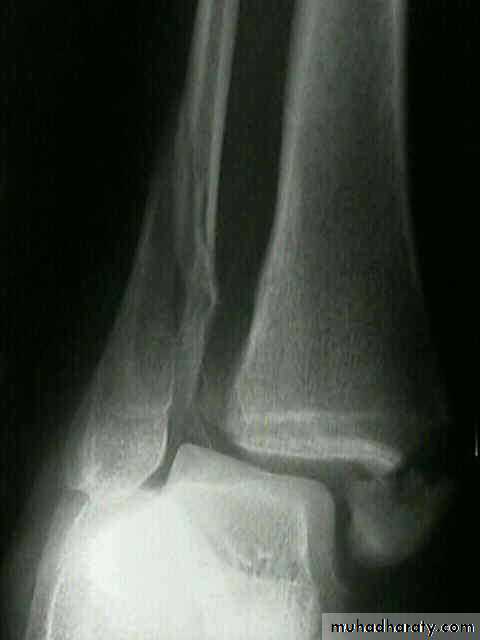

Fractures around the ankle

The bones forming the ankle mortise are injured more often than any other bone except the lower end of the radius. In the past they were often grouped together loosely under the general title is still used occasionally‘ Pott's fracture’.Types:

Fractures ankle

Clinically: there is history of twisting injury of ankle followed by severe pain, inability to stand, swelling, bruises, deformity & tenderness.

X ray: it is essential to do anteroposterior, lateral and mortise views (The AP mortise view is done with the leg internally rotated 15-20o ,This view permits examination of the articular space (clear space). The width of the clear space between the talus and the articular surfaces of the medial malleolus, the tibial plafond and the lateral malleolus should be equal.

X- ray shows the type of fractures, Any shift, tilt or displacement in talus is serious, If the fibular fractures above the tibiofibular joint there must be a diastasis.